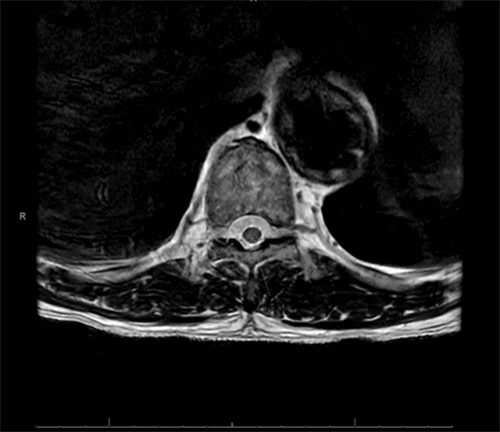

Based on these findings, he was diagnosed with a T8 level left-sided Brown-Séquard syndrome (BSS). Magnetic resonance imaging (MRI) revealed hyperintensity at T6-T8, suggestive of spinal cord ischemia (SCI) (Figure 3). The patient’s lumbar drain was replaced on POD 3. Vasopressors were administered to maintain a goal systolic blood pressure above 150 mm Hg while aiming to keep the intraspinal pressure below 10 mm Hg. The lumbar drain was removed on POD 7 after minimal improvement in his symptoms.

Figure 3. T2-weighted MRI with Short Tau Inversion Recovery (STIR) Hyperintensity at T6-T8. Published with Permission